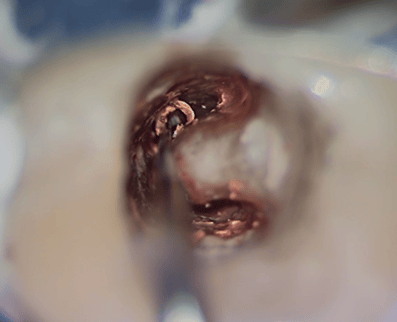

このような状態になるまで、根管の中を綺麗にしていきます。実はこの作業は非常に難しいです。図の右の凸部は歯なのですが、この裏には歯槽骨(骨)が入り込んでいて、薄皮1枚みたいな状態です。これに穴をあけると、また別の問題が生じます。